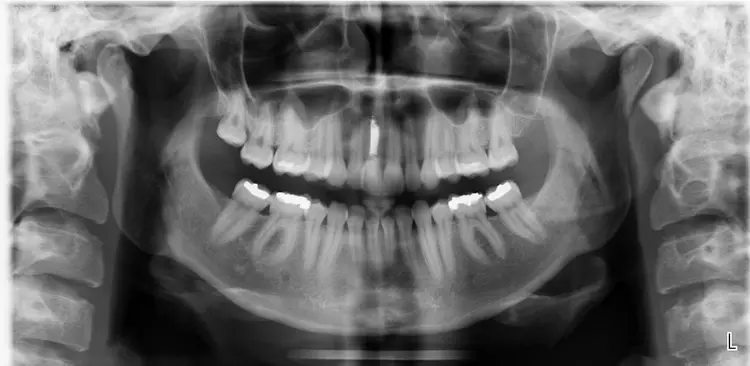

Auffällig war der Taschenbefund mit 9 mm bukkal und palatinal an Zahn 11, der auf eine Längsfraktur hindeutete. Im Rahmen der radiologischen Diagnostik wurde ein Orthopanthomogramm (Abb. 1) und ein Zahnfilm regio 11 (Abb. 2) erstellt mit sichtbarer periapikaler Aufhellung regio 11.

Zahnklinik Bochum